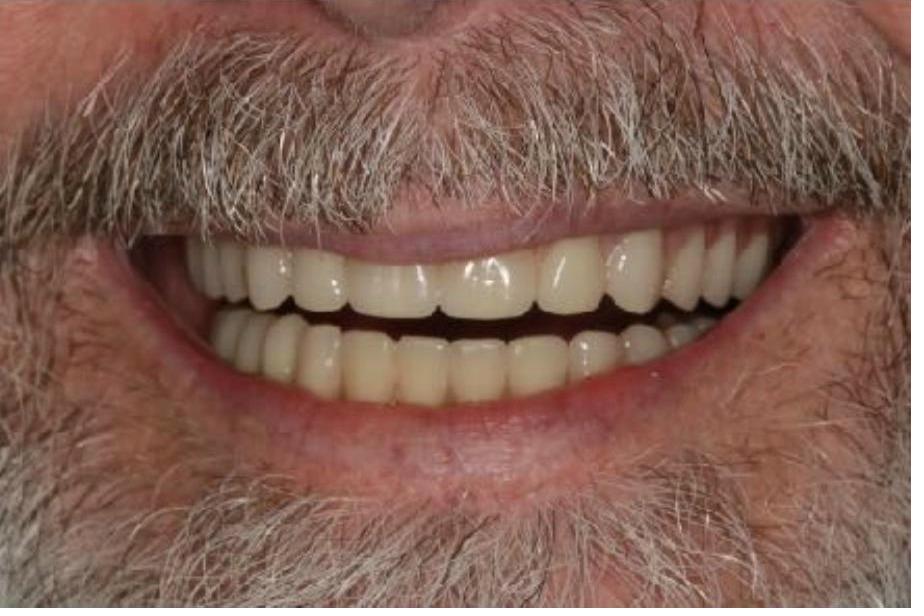

To improve this patient's dental health, esthetics and function, upper and lower implants were placed. I then fabricated an upper screw-retained implant bridge and a lower Overdenture, giving this patient back his smile and function. The patient was thrilled with the result and exclaimed "It looks good! I'll have all the women chasing me! I'd marry me if I wasn't already married!"

To improve this patient's dental health, esthetics and function, upper and lower implants were placed. I then fabricated an upper screw-retained implant bridge and a lower Overdenture, giving this patient back his smile and function. The patient was thrilled with the result and exclaimed "It looks good! I'll have all the women chasing me! I'd marry me if I wasn't already married!"